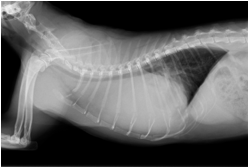

↑術後約1週間の胸部レントゲン

大きな手術でありましたが、約1週間の入院を経て無事に退院し、その後は通常通りの生活を送れています。この子のようにちょっと咳をするなどの軽い症状でも、意外と大きな病気が潜んでいることもあります。ただし、早期に病気を見つけてあげて早期に治療することで、良好な状態を維持することや完治を目指すこともできます。少しでも変わったことや気になることがあれば何でもご相談してください。